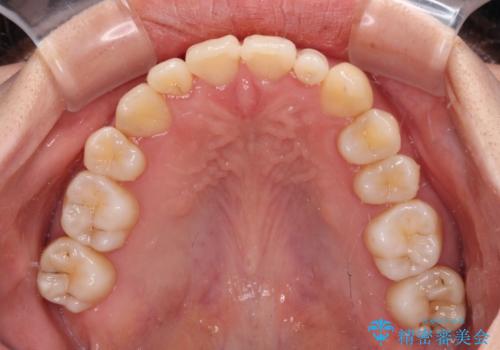

八重歯の抜歯矯正 補助装置を用いたインビザライン矯正

非常にしっかりとマウスピースを装着してくださいましたが、前歯の排列がなかなか仕上がらずに期間がかかってしまいました。